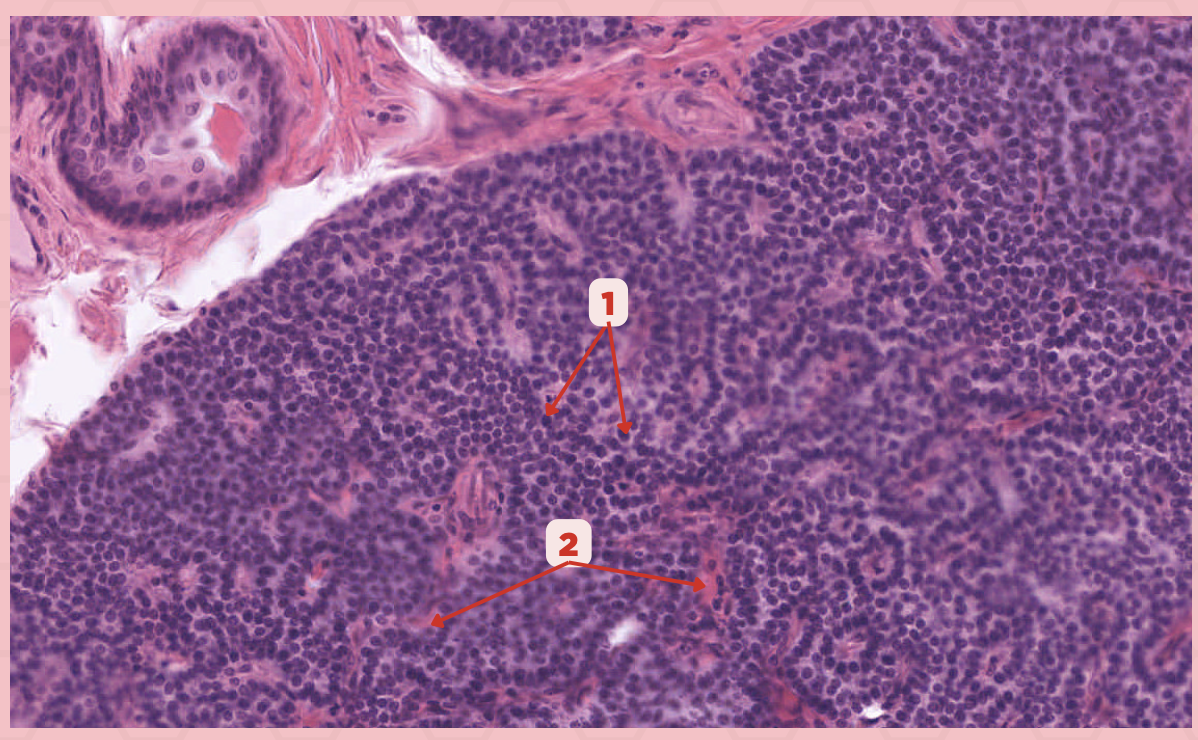

Parathyroid

Identify the specimen.

Chief Cells

Identify the structure labeled as 1. This comprise the majority of cells in the parathyroid gland.

Septa

Identify the structure labeled as 2.

Parathyroid hormones

What hormones are synthesized and secreted by the cell in Pointer #1?

Parathyroid

Identify the specimen.

Chief Cells

Identify the specimen labeled as 1.

Oxyphil Cells

Identify the specimen labeled as 2.

Adipocytes

Identify the specimen labeled as 3.

Capillaries

Identify the specimen labeled as 4.

Newborns

Pointer #2 is hardly present in the parathyroid glands of _____.